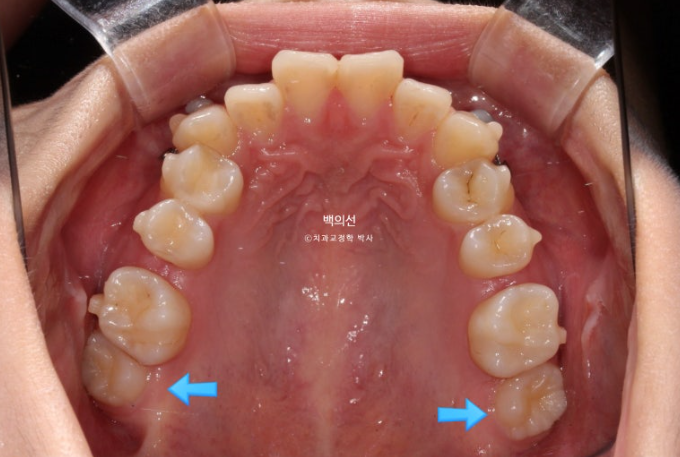

23.05

송곳니 덧니가 심한편입니다.

맨 뒤 큰어금니는 뒤로 나있습니다.

파란 화살표 위 마지막 큰어금니는 매복된 사랑니에 눌려 사랑니를 발치하지 않으면 바로세우기 힘든상황입니다.

그런데 씨티를 찍어보니 매복된 사랑니가 상악동과 닿아있어 발치가 쉽지 않은 상황입니다.

무리하게 발치를 시도했다가 상악동천공 등의 부작용이 생길 수 있습니다.